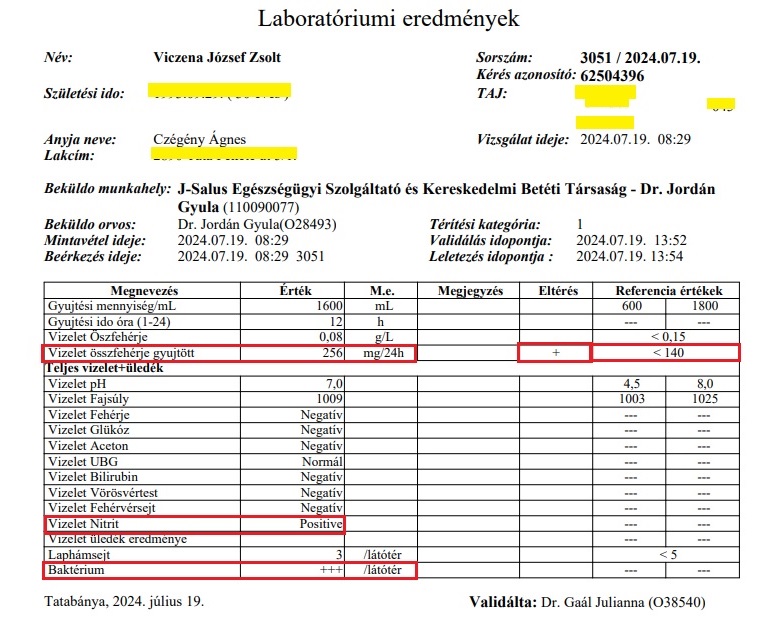

A vesekőzúzást (ESWL) tágult, gyulladt vesén végezték. Az operációnál, mert hogy ez annak számít, nem volt jelen az orvos! (De később a papírt kiküldte Dr Mosonyi Péter egy kolléganőjével az orvosi szobából, ekkor már operatőrként aláírva!) Ezért a technikus és a nővér tanácstalanok voltak, mit tegyenek egy ilyen gyulladt, tágult vesével, amit ultrahanggal láttak, elvégezzék-e a beavatkozást. Végül a kőzúzás mellett döntöttek. A fiam veséje az egyik legnagyobb mennyiséget, 3000-es ütésszámot kapta! Három hét múlva a fiam észrevette, hogy vérvizelése van. Odaadta az edényt, hogy vigyem le a háziorvosához, Dr Reisz Kornéliához, hogy adjon egy beutalót rá, hogy gyorsan le tudjuk adni. Megtagadta a beutalót, azt mondta, majd az asszisztens tesztcsíkkal megnézi. Aki pedig azt állapította meg, hogy „nincs benne vér, picike fehérje, de vér nincs.” A fiam otthon felrobbant a hülyének nézéstől, felöltözött és a már akkor is rossz állapotában maga vitte el a tatabányai Synlab-hoz leadni ugyanezt a vizeletet. A „nincs vér” igazából 3 keresztes vérvizelés és 100-szoros vörösvörtest/látótér volt. Már ekkor elkezdődött az, amiből aztán ahogy a cikk címe is utal rá, egy horrortörténet lett!

Innentől kezdve a fiammal 31-szer mentünk orvosokhoz kórházakba, klinikákra, sürgősségikre, ügyeletekre, kínunkban még nefrológus docens magánrendelésére is, de azt éltük meg, hogy folyamatos vérvizelése és nagyon súlyos vesefájdalma és tünetei ellenére mintha csak náthával lenne ott, nem veszik semmibe, nem adtak antibiotikum kezelést, sem kórházi felvételt és kezelést – utóbbi lett volna az egyetlen lépés, aminek ilyenkor azonnal történnie kellett volna! Egyszerűen nem értettük, hogy mi folyik itt, nem láttuk be, hogy mi lesz ebből így. A fiam megszállottan csináltatta a tatabányai Synlabnál a vizeletvizsgálatokat, mert nem volt orvosi kontrollunk. Ez a „szerencse”, mert rengeteg bizonyító lelete lett, szemben az állami négy-öt lelettel, amelyek nagy része egyébként szintén súlyos bizonyíték mellette.

Később, júliusban Zsolt új háziorvosa beutalója által készült 24 órás vizeletgyűjtés is, amelynek eredménye közel 2-szeres összfehérje szintet mutatott a vizeletben a megengedett maximumhoz képest (fehérjevizelés = krónikus veseelégtelenség, vesebetegség)! Beleüldözték a fiamat! Emlékezzünk az összeomlás (szeptikus állapot) előtt két héttel, a március 13-ai mintában ez az érték 7-szerese volt a felső határértéknek. És pozitív lett ismét a hugyúti fertőzés, vesefertőzés egyik legfontosabb jelzője, a Vizelet Nitrit, emellett 3 keresztes baktériumvizelést igazolt. Ez már 6 (!) hónappal a februári összeomlás, 1000-szeres vérvizelési (vvt) értékek után volt. A kórházi kezelés megtagadásával, elmulasztásával bennhagyták Zsolt szervezetében, veséiben a fertőzést, aminek következménye már veseelégtelenségi paraméterekben is megmutatkozott: